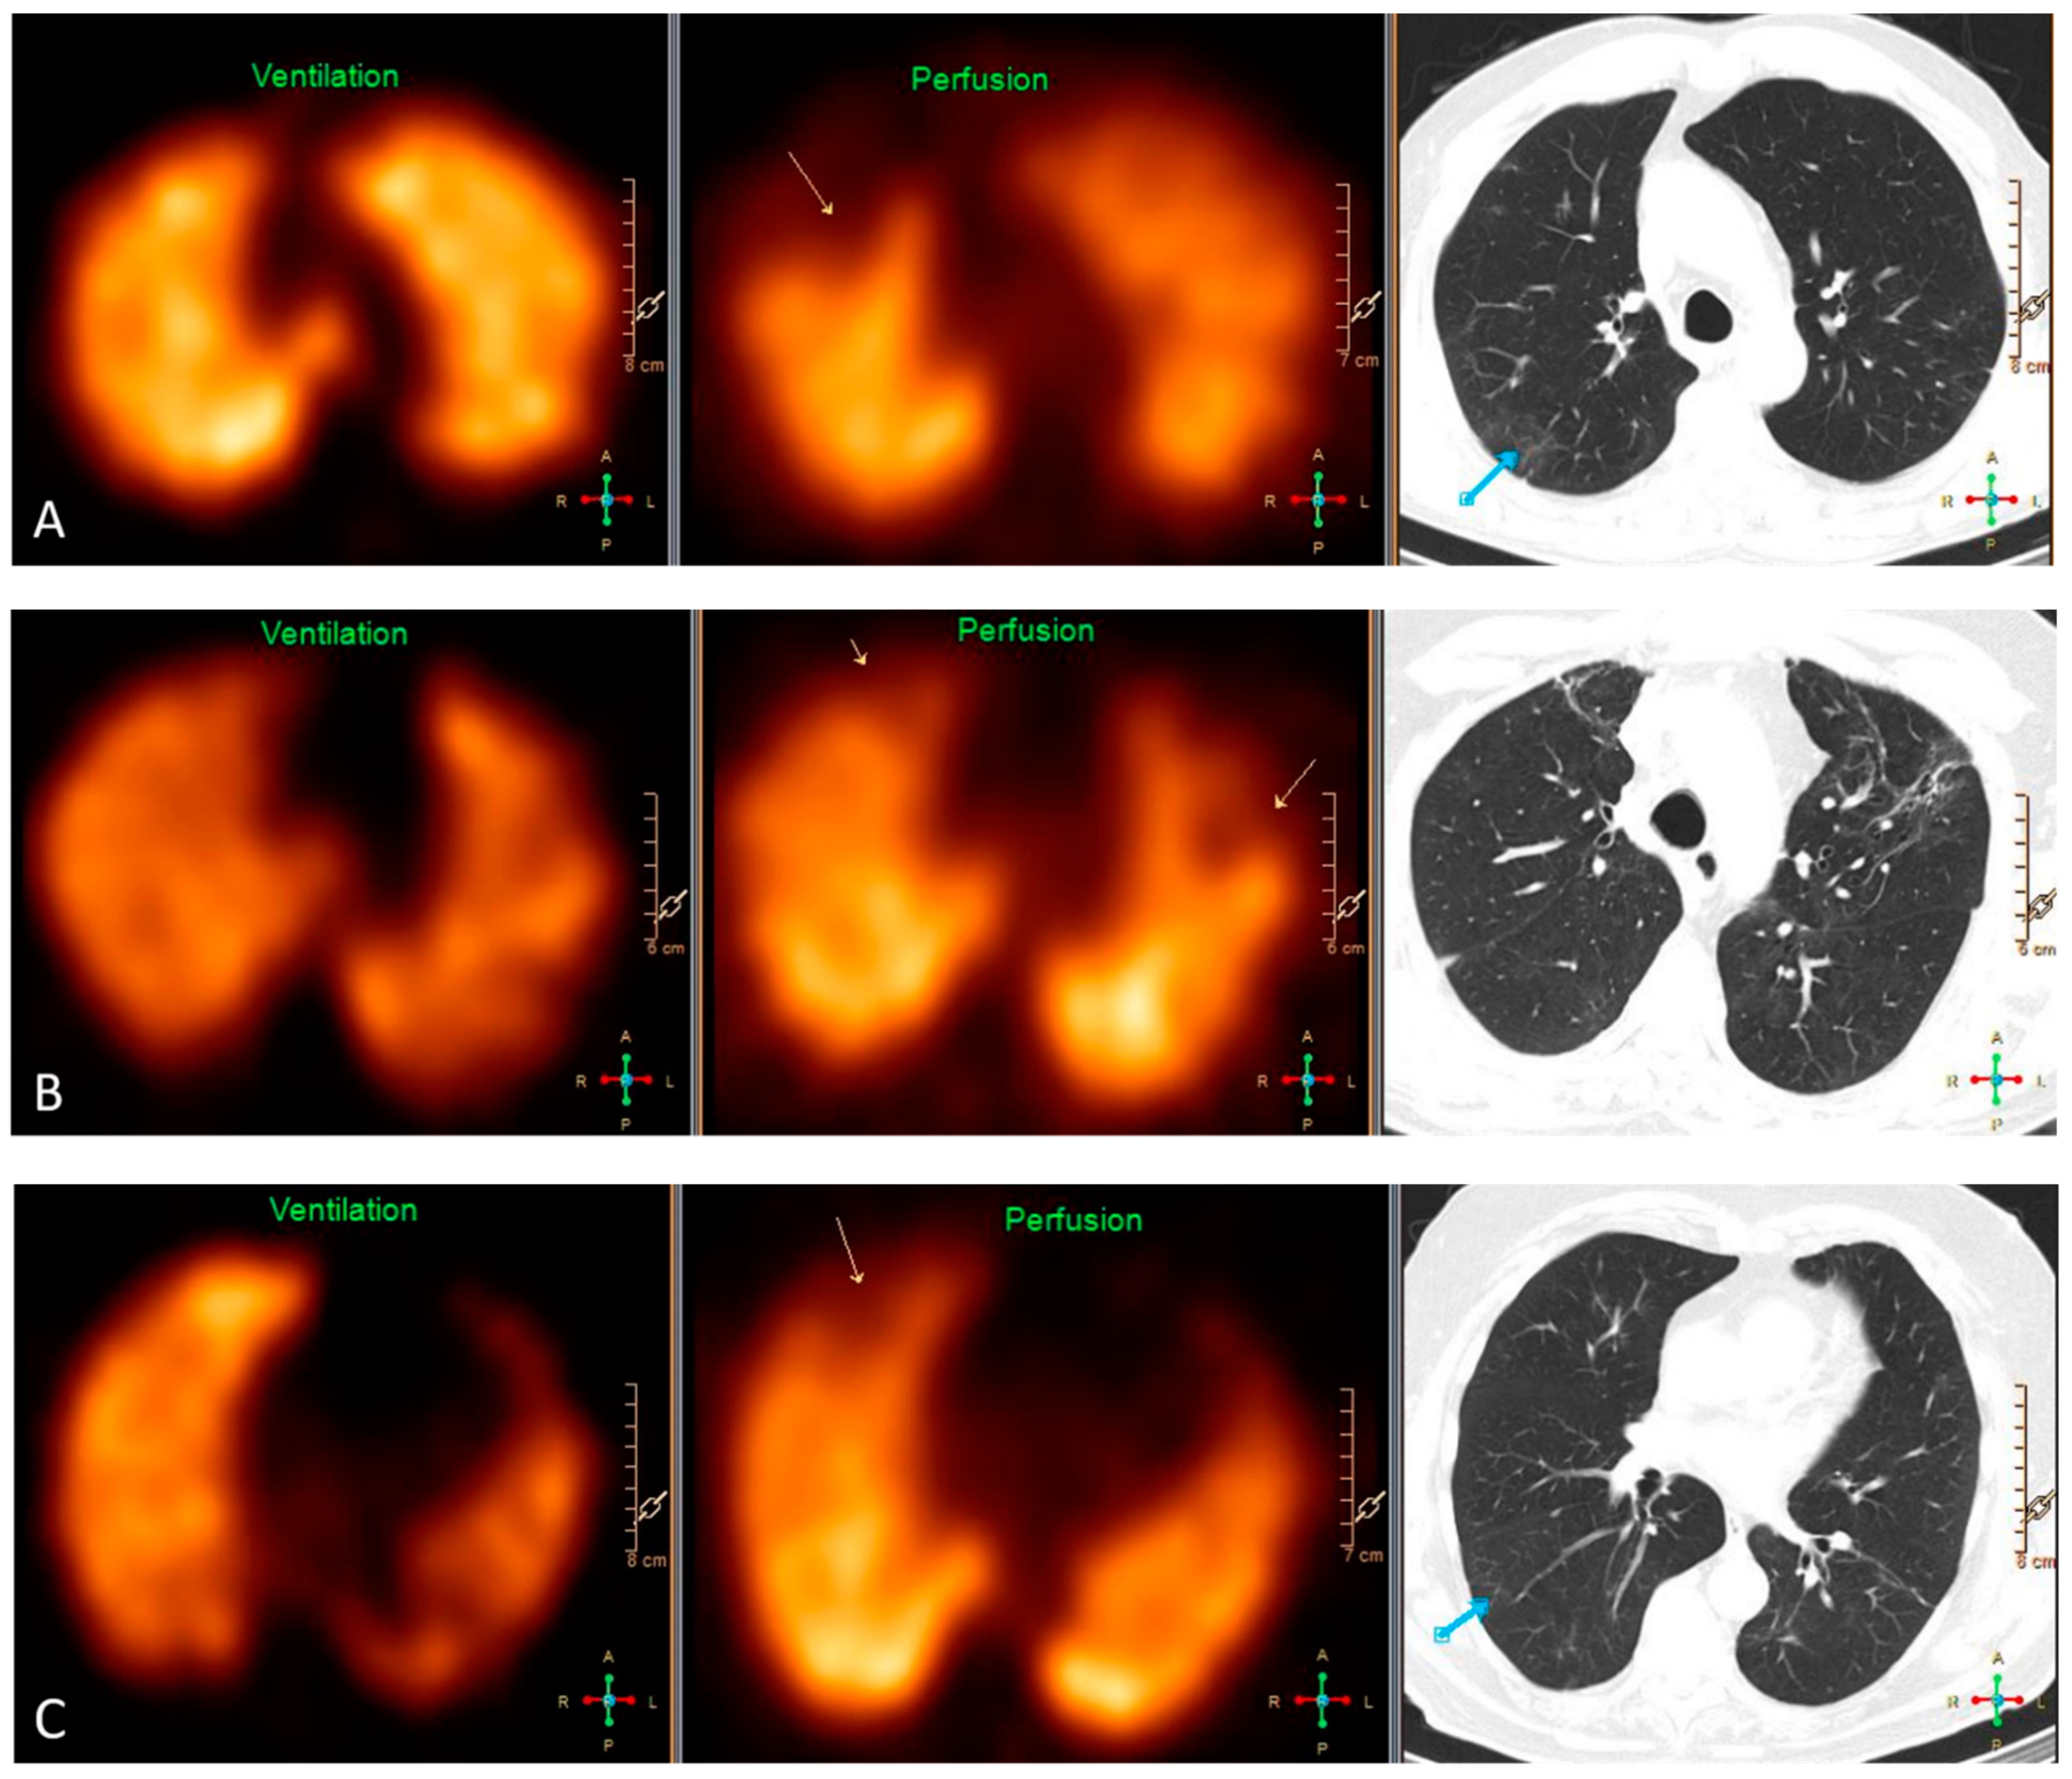

3.3. VQ SPECT